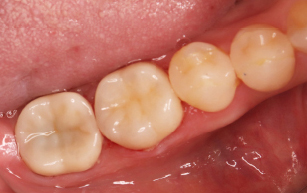

- 32 メタルインレー除去、ハイブリッドセラミックインレー形成印象の症例

| 主訴 | 銀歯を白くしたい |

| 治療内容 | 金属除去、つめ物かぶせ物治療 |

| 治療期間 | 2週間 |

| 治療費用 | 総額 330,000円(税込) つめ物(セラミックインレー) 55,000円(税込) ×2 かぶせ物(ジルコニアステインクラウン) 110,000円(税込) ×2 |

| 副作用等 | 神経の治療 |

| 治療方針 | 金属を除去し中の虫歯を しっかりとりきりセラミックのつめ物 |

| 特記事項 | 金属の中は虫歯になっており、 症状がなかったが神経まで達していて 神経の治療が必要になったケースです。 |

| 担当者所見 | 一本ずつではなく同時にブロックで型取り、 色味合わせを行なったため精度、 審美面どちらも患者さまには満足していただけました。 |